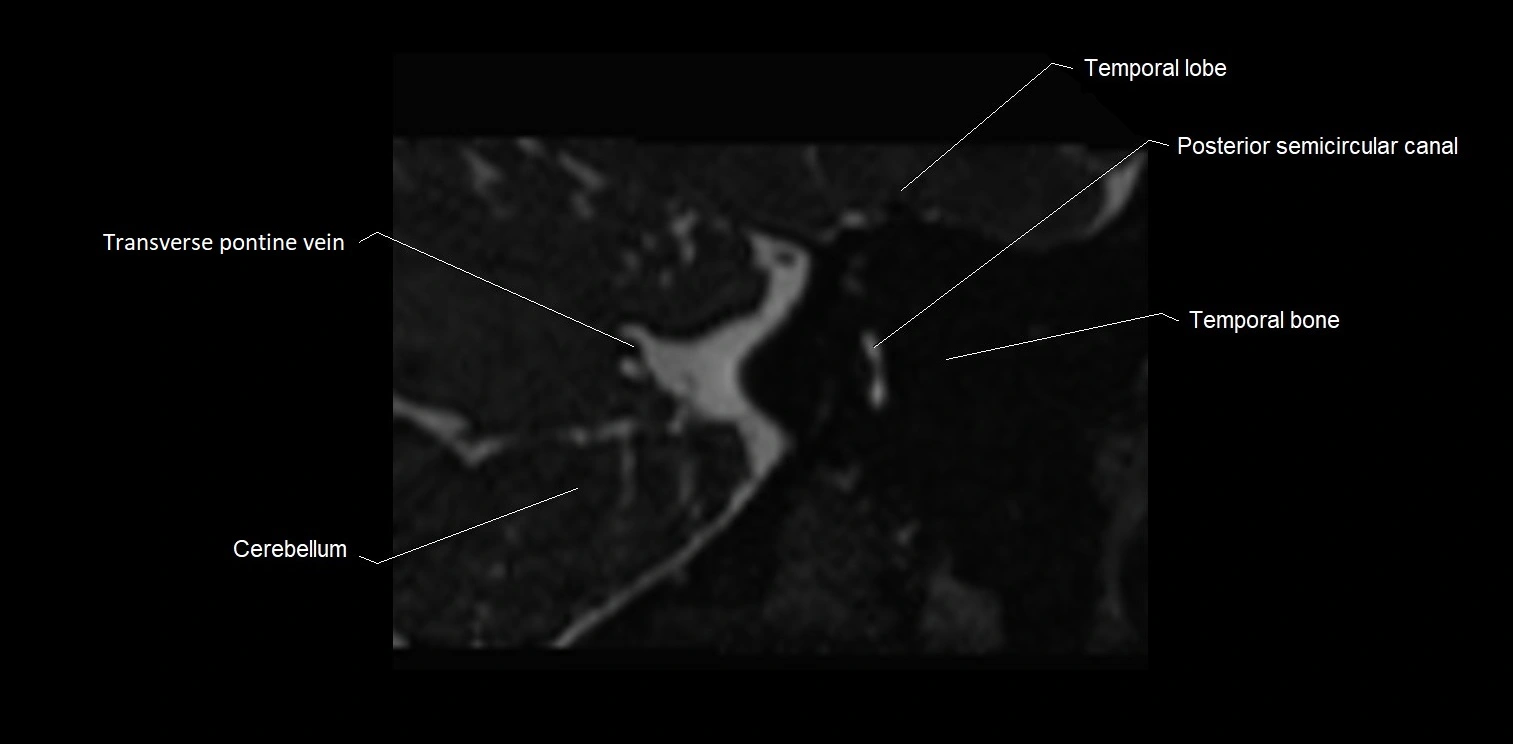

MRI Appearance

• The abducens nerve is a small, thin, linear structure

• Best visualized on high-resolution T2-weighted 3D MRI sequences (e.g., FIESTA or CISS)

• Seen as a hypointense (dark) line running from the brainstem at the pontomedullary junction, traversing the prepontine cistern, and entering Dorello’s canal under the petrosphenoidal ligament, then into the cavernous sinus, and finally the orbit

• May be challenging to visualize in standard MRI due to its small size

• Pathology may be inferred by absence, displacement, or enhancement of the nerve